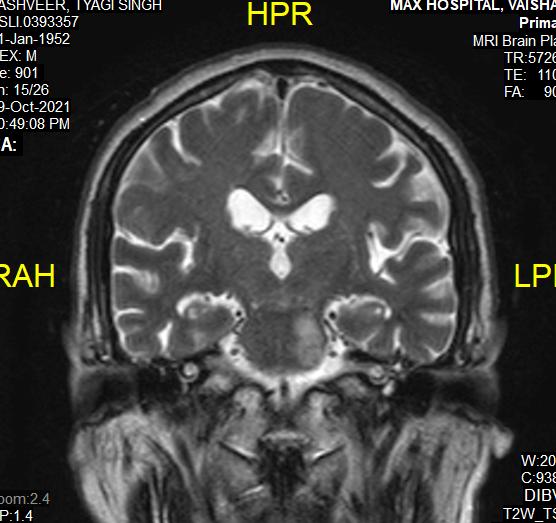

histopathology or polymerase chain reaction in a Patient with a clinical diagnosis of Invasive Mucormycosis. Cases were considered COVID-19 associated if the patient received a positive Reverse Transcription Polymerase Chain Reaction or Antigen test result for SARS-CoV-2 during the 60 days preceding the mucor diagnosis1.” Every patient is evaluated at presentation with detailed history, Clinical examination, ENT, Ophthalmic and Neurological examination to assess the extent of disease. Patients’ occupational history, personal habits, Socio-economic status (Modified B G Prasad Scale), prior treatment, vaccination status & COVID status were recorded at admission. Patients with pre-existing Facial Nerve palsy due to other known causes like cerebrovascular accident, non-covid intracranial, temporal bone, parotid pathology were excluded. Facial soft tissue involvement if mimicking Facial Palsy was also excluded. Facial Nerve function assessment was done in detail. It was first subdivided into upper and lower Motor Neuron type of deficit. LMN lesions were further graded by the House Brackmann Scoring System. Topo-diagnostic tests like Schirmer test, Stapedial reflex test and Taste sensation were assessed as far as practicable. Diagnostic Nasal Endoscopy (DNE) and Radiological assessment (Computed Tomography and Magnetic Resonance Scan of Head, Neck and Orbit) was done. Patients undergoing surgical debridement and those considered for conservative management were followed up at three months to check for change in the state of Facial Palsy. All interventions were done maintaining institutional and ICMR COVID protocol.

Radiological assessment in the form of Magnetic Resonance Imaging and Computed Tomography of the diseased site was done. Contrary to the clinical presentation, all of the patients (100%) had Nose and Para nasal sinus involvement. Orbit was involved in 72.72% of patients. Pterygopalatine fossa involvement and intracranial disease extension was found in 54.54% of the patients respectively. None of the patients had infra-temporal fossa and temporal bone involved by Mucor.

Fig 1Fig 2Fig 3 Fig 4Fig 5

Figs 1-5 — Photographs of patients suffering from Post COVID Mucormycosis with new onset Facial Nerve Palsy